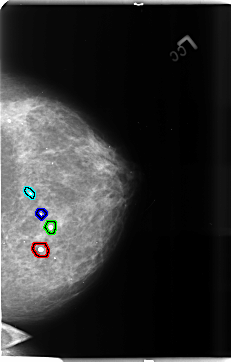

B_3684_1.LEFT_MLO

FILE: B_3684_1.LEFT_MLO.OVERLAY

TOTAL_ABNORMALITIES 6

ABNORMALITY 1

LESION_TYPE CALCIFICATION TYPE ROUND_AND_REGULAR-EGGSHELL DISTRIBUTION N/A

ASSESSMENT 2

SUBTLETY 3

PATHOLOGY BENIGN_WITHOUT_CALLBACK

TOTAL_OUTLINES 1

BOUNDARY

ABNORMALITY 2

ABNORMALITY 3

ABNORMALITY 4

ABNORMALITY 5

ABNORMALITY 6